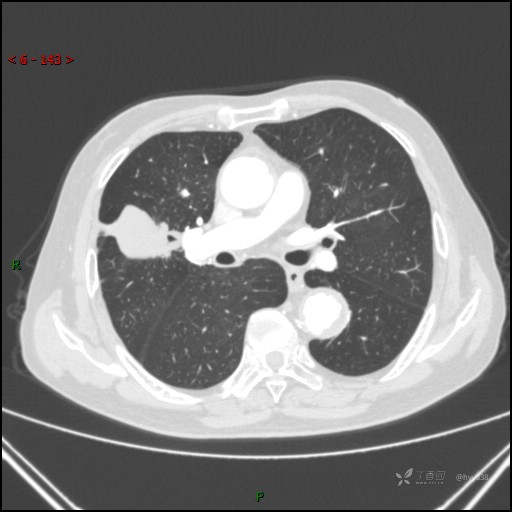

胸部CT肺窗